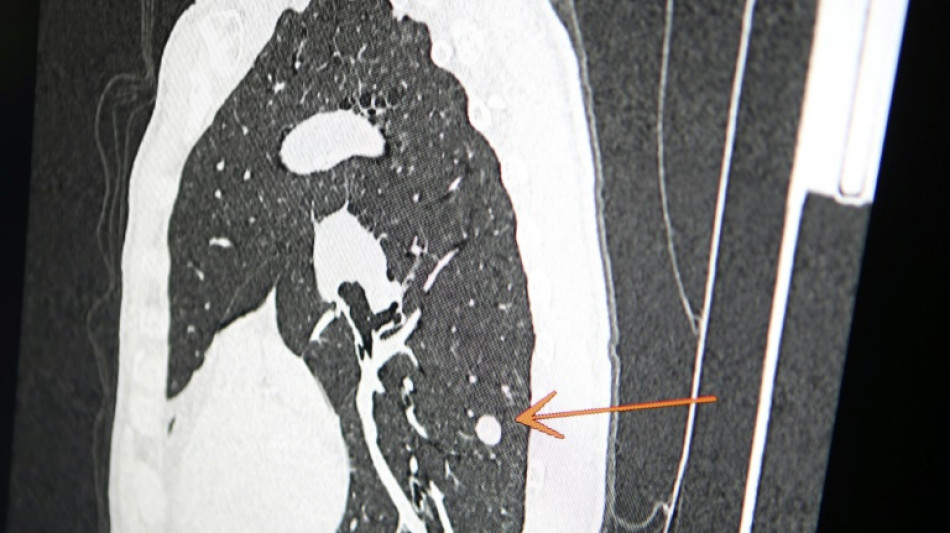

"Usted tiene cáncer", mensaje erróneo y aterrador a cientos de pacientes de una clínica en Inglaterra / Foto: © AFP/Archivos

Una clínica del norte de Inglaterra dio un gran susto a cientos de pacientes al enviar el mensaje "diagnóstico: cáncer de pulmón agresivo con metástasis" en lugar de sus buenos deseos de Navidad, informó el diario The Sun el jueves.

El 23 de diciembre a las 15H49, los pacientes de este centro de salud de Askern, cerca de la ciudad de Doncaster, recibieron un mensaje de texto en su teléfono informándoles de este diagnóstico, pidiéndoles que rellenaran los formularios correspondientes y concluyendo: "Gracias".

Según The Sun, entre los destinatarios del mensaje figuraba Chris Reed, un padre de familia de 57 años, que esperaba resultados de análisis para determinar si padecía cáncer de pulmón.